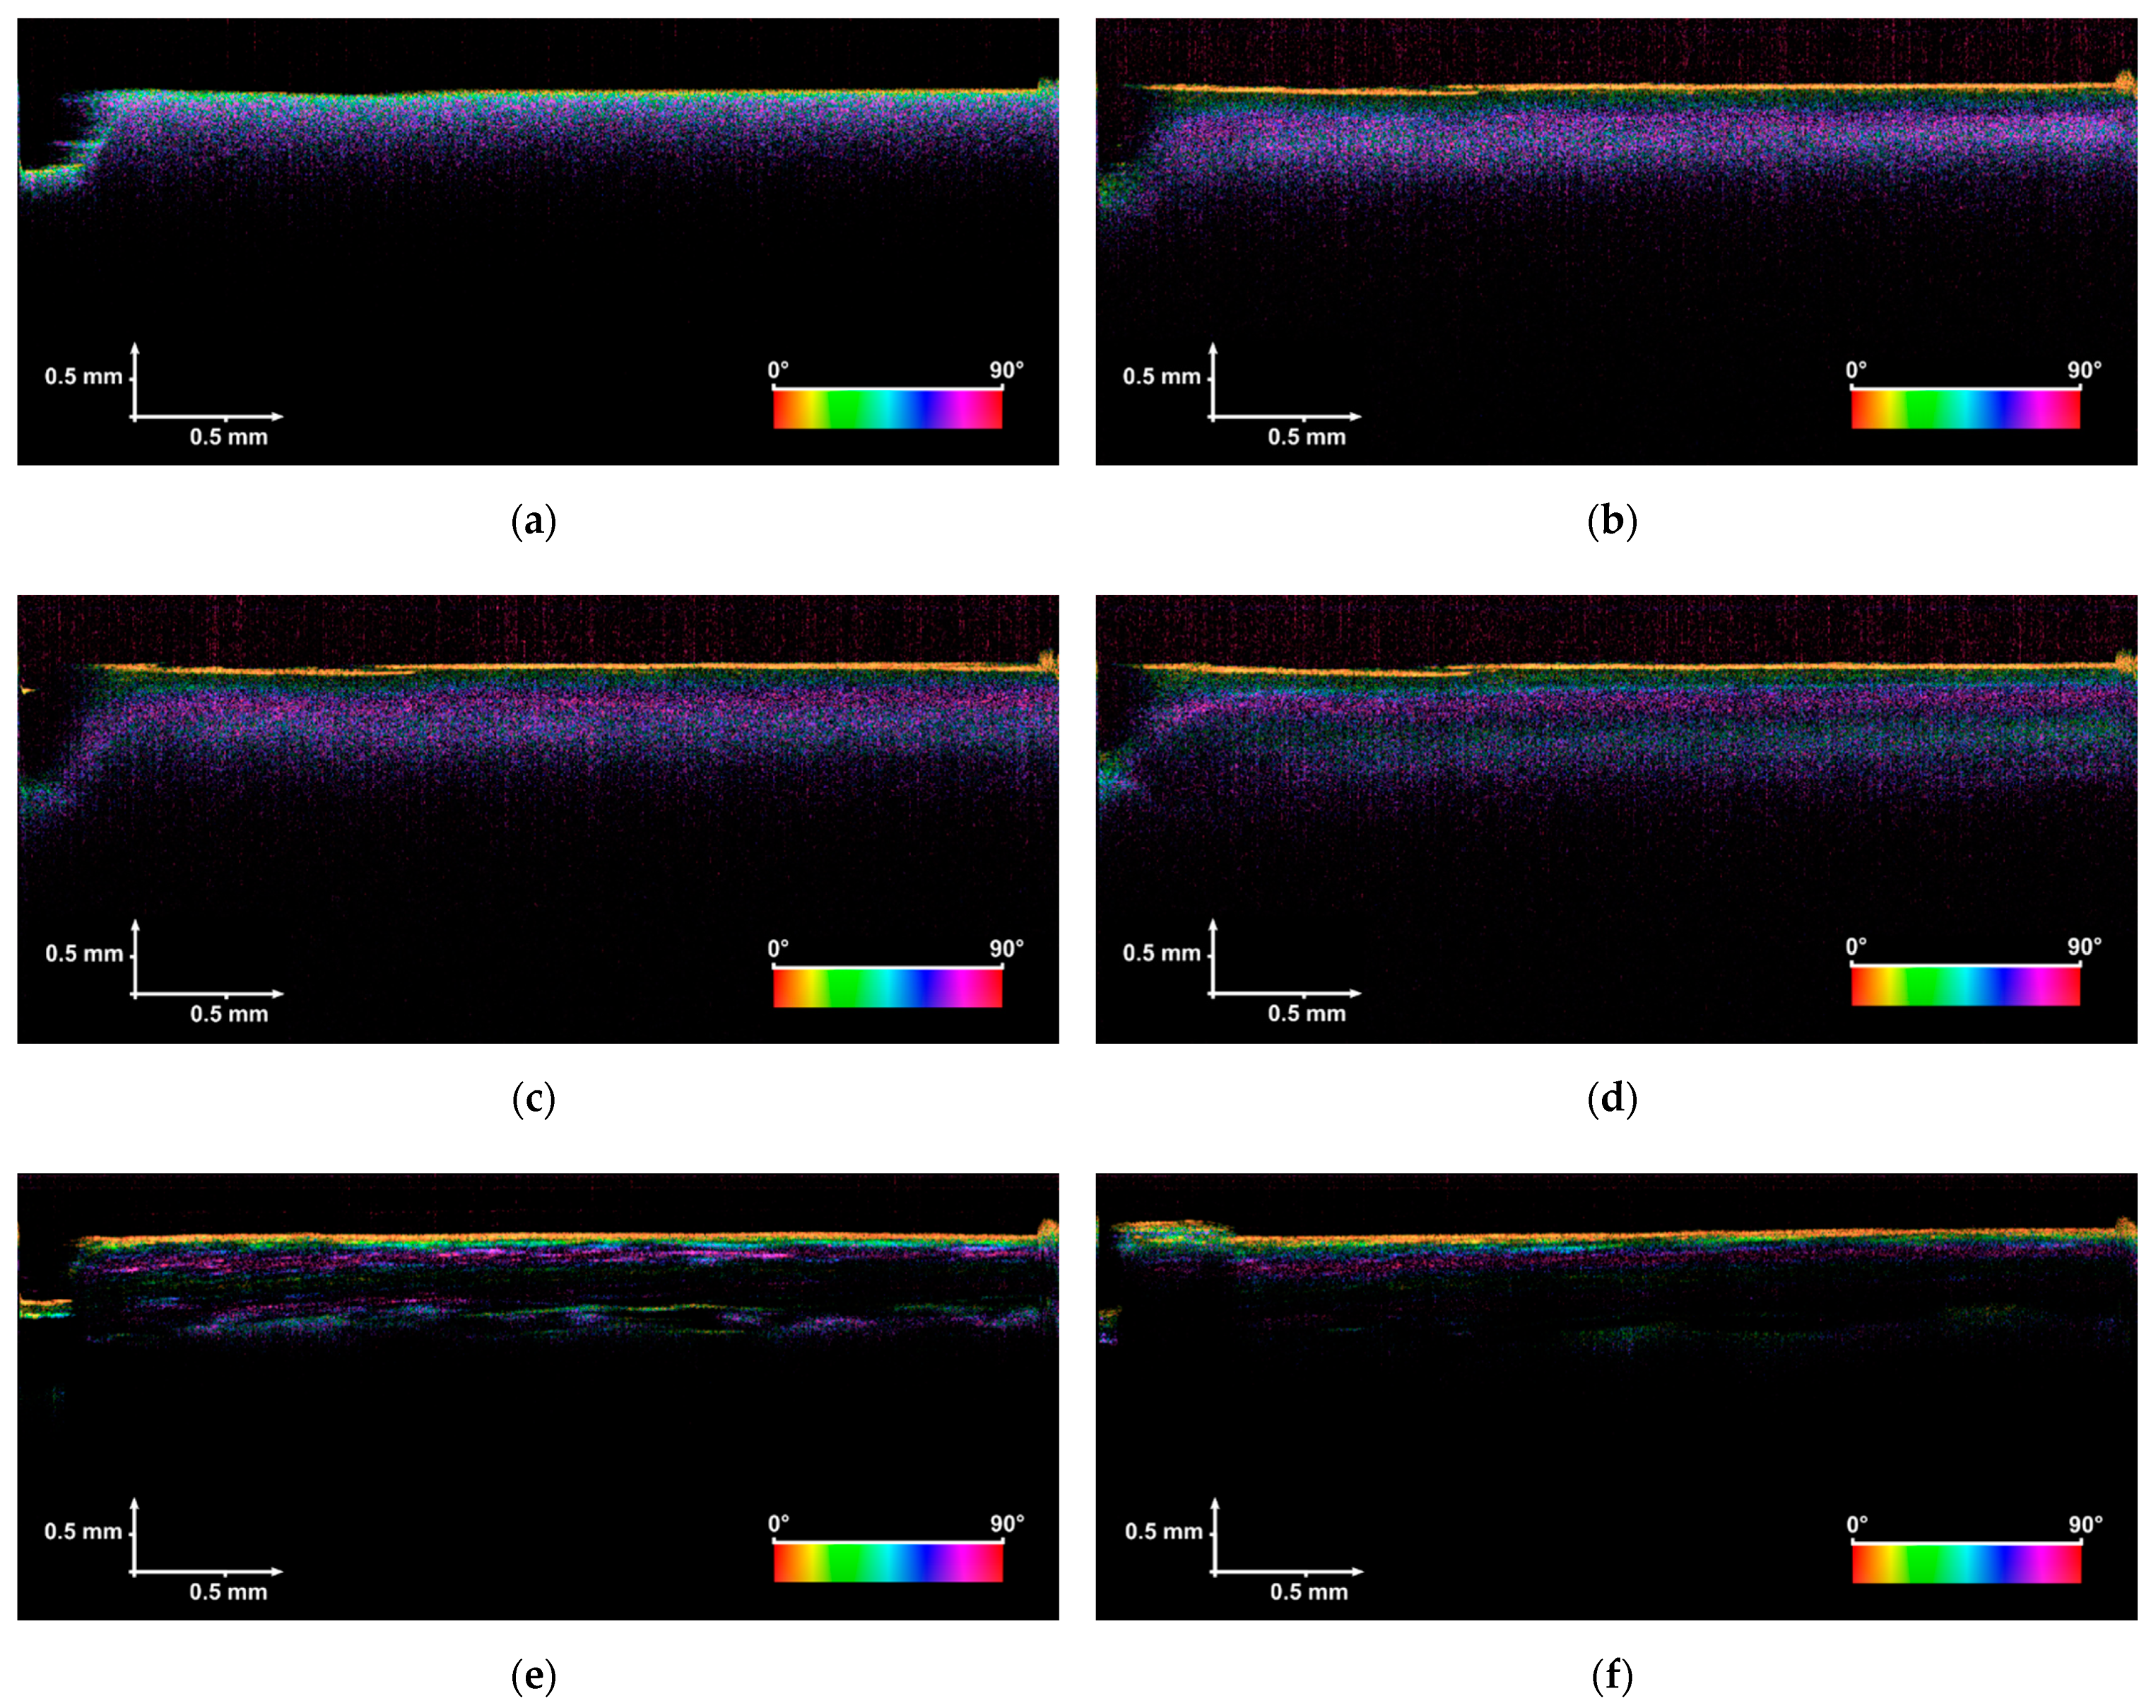

3.1. Polarization-Sensitive Optical Coherence Tomography (PS-OCT) Measurements

3.4. Raman Spectroscopy